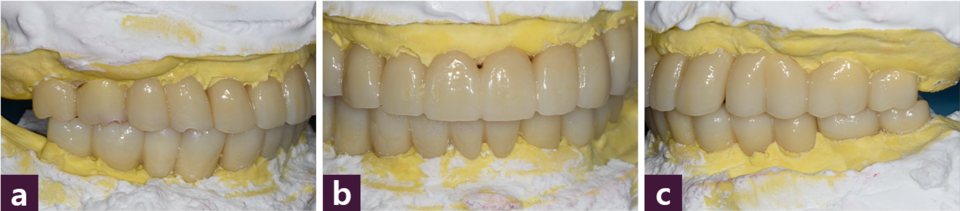

완성된 상하 보철물을 구강내에 fit-checker를 이용하여 가착한 후 악간 관계를 채 득하고 pick up type 인상 채득 한 다음 반조절성 교합기에 리마운팅하여 교합조정을 시행해 전방 및 측방운동시 군기능 교합양식을 부여하였다 [그림 11].

완성된 최종 보철물을 구강내에 위치시키고 추가적인 교합조정 후 레진 강화형 글라스 아이오노머 시멘트(RelyX Luting cement, 3M, USA)로 최종 접착하였다[사진 12~15].